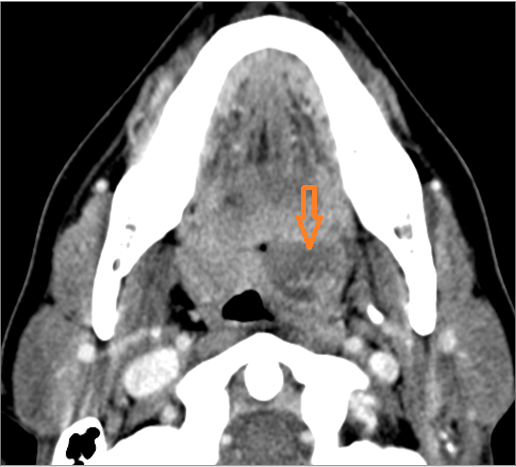

There is suppurative cervical lymphadenopathy. [Yes/No]